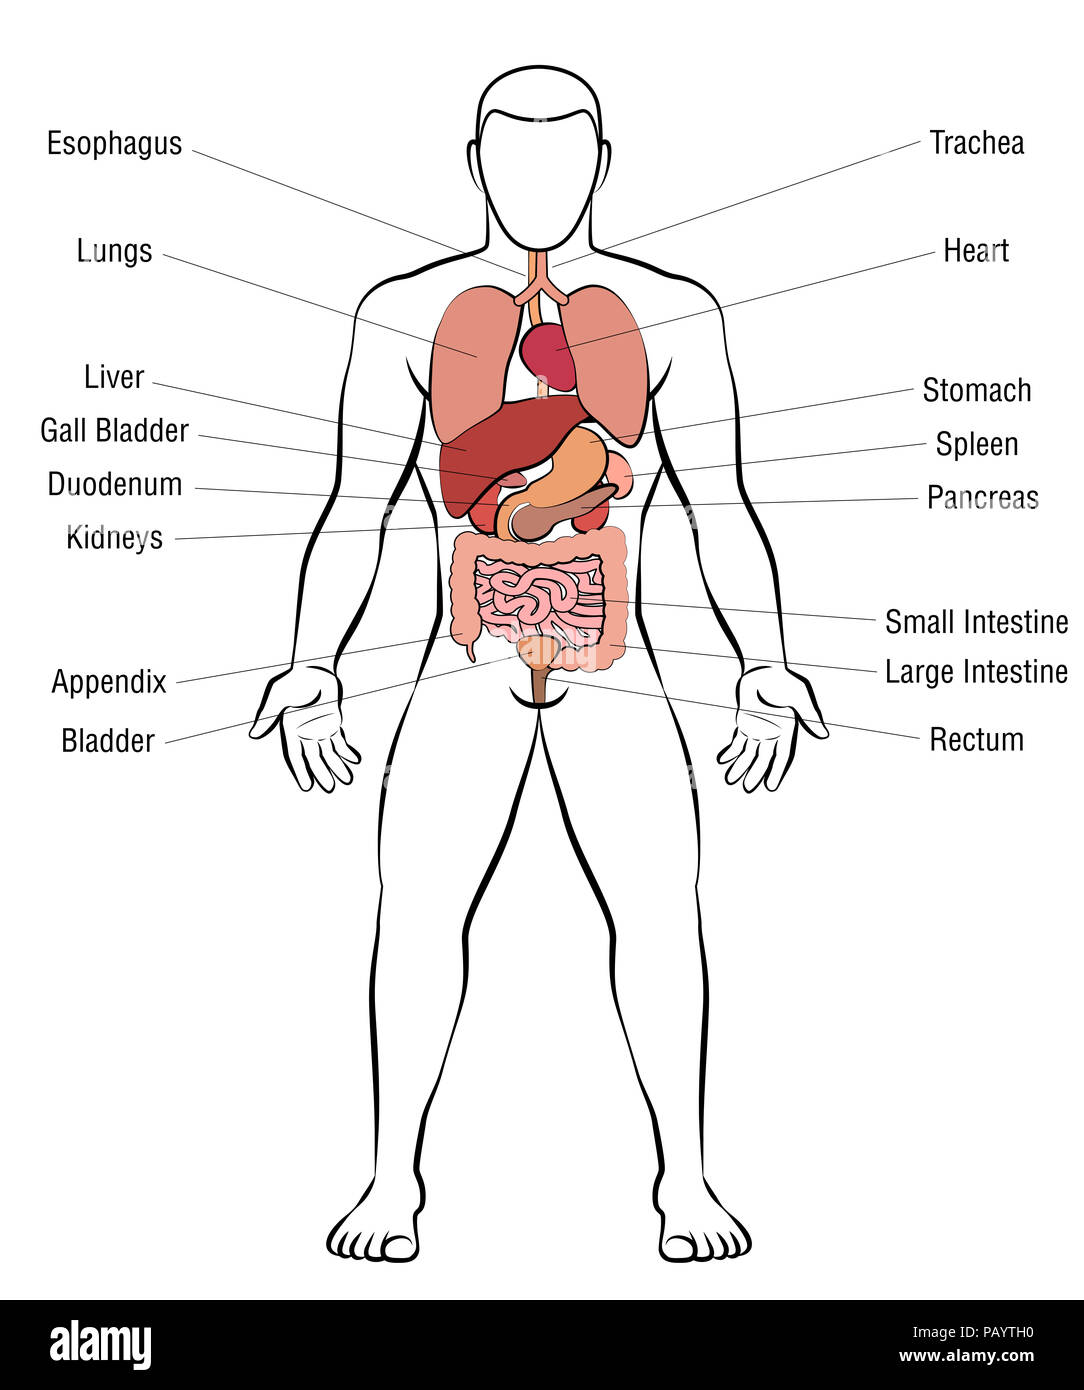

RFPAYTH0–Innere Organe, männlichen Körper - schematische Darstellung der menschlichen Anatomie Illustration - auf weißem Hintergrund.